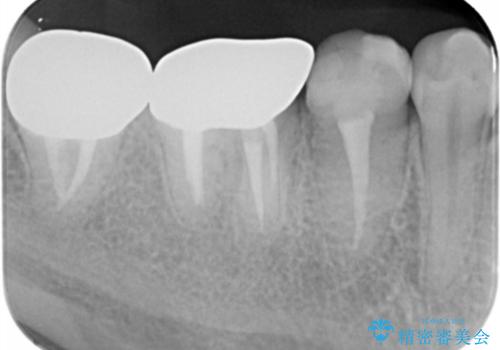

奥歯は既に根管治療が為されクラウンを装着する必要性がある状態ですが、歯の高さが低くクラウンの安定性・強度を担保するために歯周外科を行う治療計画としました。

歯周外科を行うことで、歯ぐきの位置を下げ歯の高さを作り出し安定したクラウンの装着が可能となります。また同時に舌の邪魔となっていた骨隆起の除去を行うこととしました。